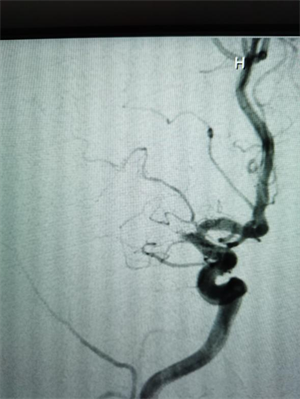

元宵节凌晨4点,60岁的胡先生因左侧肢体无力、言语不清,被紧急转送至我院。经检查,胡先生右侧脑梗死,且仍有大片缺血低灌注区域,右侧大脑中动脉完全闭塞,情况十分危急。神经内科介入团队迅速启动卒中绿色通道,立即为其行大脑中动脉急诊再通手术。术中,医生通过球囊扩张并置入血管支架,成功实现血管再通。当晚,胡先生左侧上下肢无力症状明显改善,肢体力量恢复,言语也变得清晰。

△图二:手术后闭塞的大脑中动脉已再通